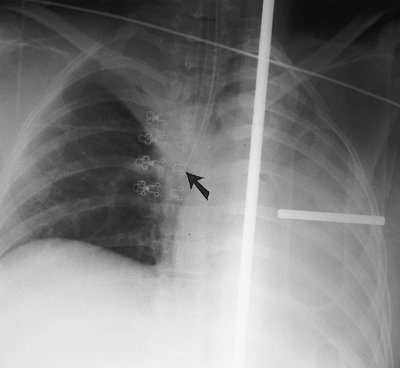

Coiling or redundancy of pulmonary artery catheter tubing in the right side of the heart can irritate the myocardial conduction bundle and result in dysrhythmias (Fig. 5-10). Other potential complications of pulmonary artery catheter placement

P.68

include pulmonary artery rupture (leading to pulmonary hemorrhage), pulmonary artery pseudoaneurysm (Figs. 5-11 and 5-12), fistulae between the pulmonary artery and the bronchial tree, intracardiac knotting of the catheter, and balloon rupture (Table 5-2). Complications that can occur with CVP catheter placement can also occur with pulmonary artery catheter placement (Fig. 5-13).

FIGURE 5-10. Looping of pulmonary artery catheter tubing. AP chest radiograph shows looping of the pulmonary artery catheter tubing (arrow) over the expected right atrium. This redundancy of catheter tubing can lead to dysrhythmias.